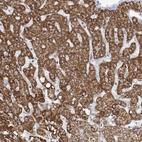

Immunohistochemistry analysis in human liver and skeletal muscle tissues using HPA030947 antibody. Corresponding BDH1 RNA-seq data are presented for the same tissues.